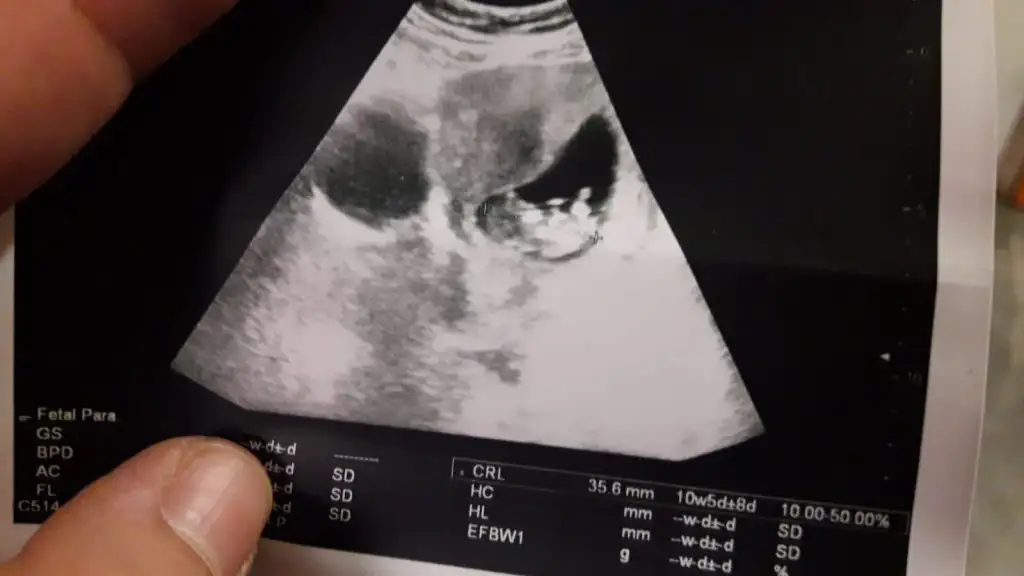

Nubu biraz kapatmış bacagı ama sanki erkek gibi başka usg varmı 11 hafta yada 12+4 den başka usgMerhabalar ben de çok araştırdım bu teoriyi kız gibi geldi bana ama sizce nedir 12+4 ten ultraEki Görüntüle 2577076 Eki Görüntüle 2577077 son

Nubu kapalı görünmüyor başka usg varmı sanki eminde değilim kız gibi

Arada kaldım yüzde altmış kız yüzde kırk erkek

Teşekkür ederim. Hayırlısı sağlıklı olsun inşallah. Doktora da sordum da bakti epey hic fikir yürütemiyorum dedi hangi resme göre yorumladınız birinde sırtı dönük gibi. Yanılıyor muyum?Arada kaldım yüzde altmış kız yüzde kırk erkek